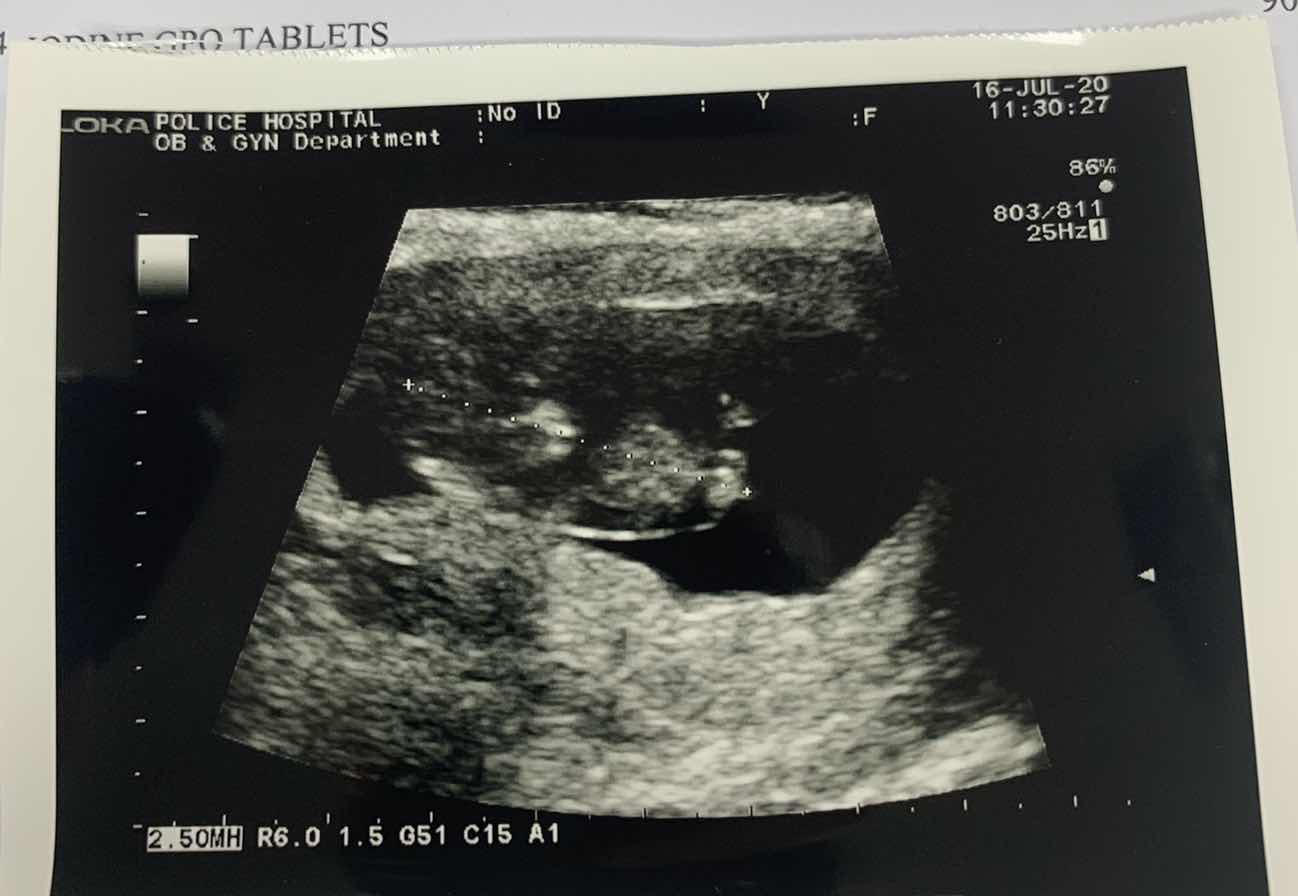

11 สัปดาห์

11 สัปดาห์ ซาวด์มาเจอลูกแบบนี้ถือว่าเขาตัวใหญ่ไหมคะหรือปกติ

ปกติจ้า นี้ตอน9สัปดาห์

ปกติจ้า เท่าๆบ้านนี้